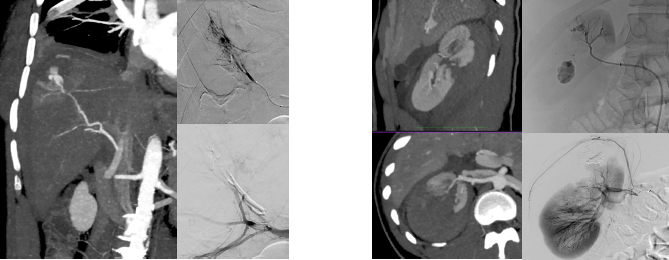

Right: A 54-year-old male presented to the emergency department following a motor vehicle accident. CT angiography demonstrated active contrast extravasation within the liver parenchyma. Superselectiveembolization with cyanoacrylate glue under conscious sedation achieved hemostasis, with no further intervention required.

Left: A 19-year-old male presented to the emergency department after a bicycle fall. CT angiography revealed a grade IV renal injury. Selective embolization of multiple renal arterial branches successfully controlled the hemorrhage, preventing life-threatening retroperitoneal bleeding and avoiding nephrectomy.